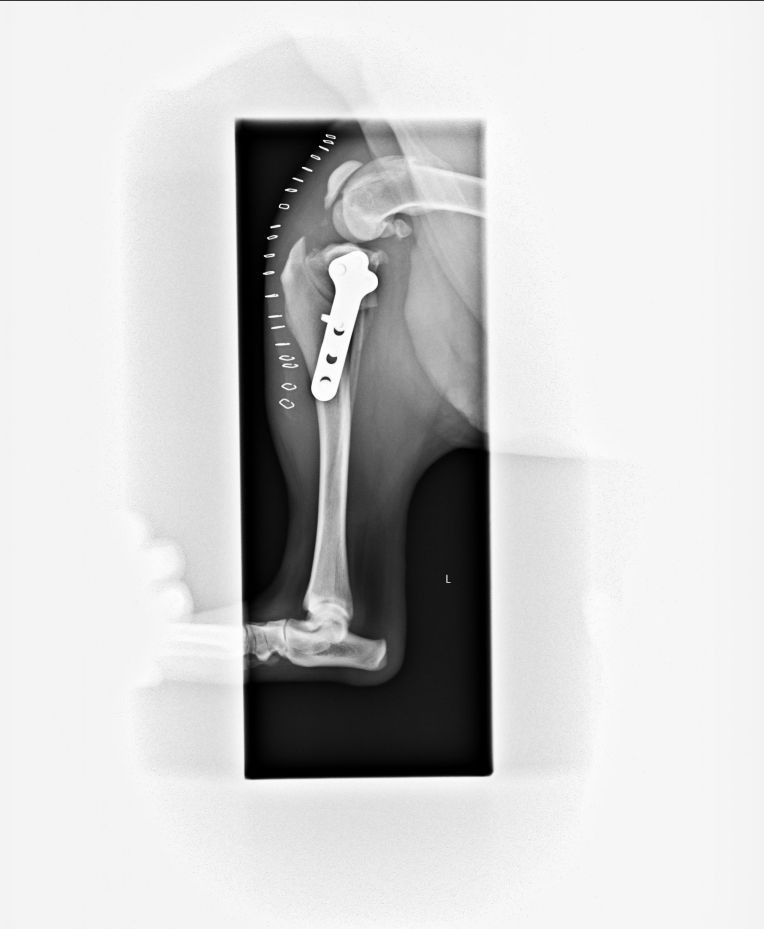

左脚の手術も前回と同じTPLO手術。

又、TPLOと同時に内方脱臼の処置も行いました。

でも、プレートもちゃんと付いたし、